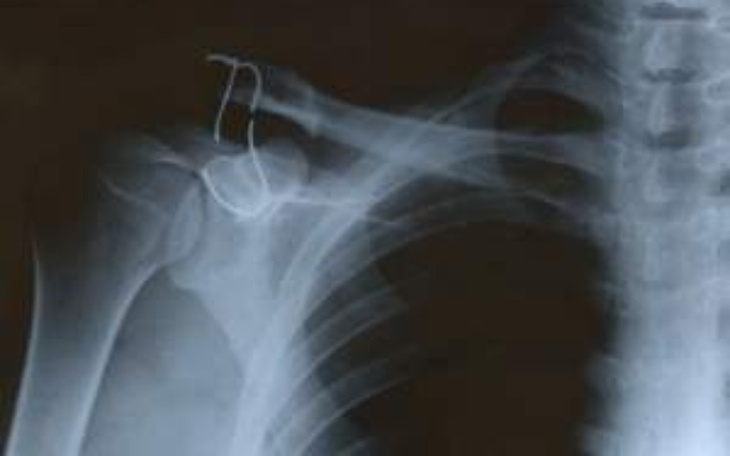

Jestem Daniel Barkowski i ostatnio złamałem bark na w-f.